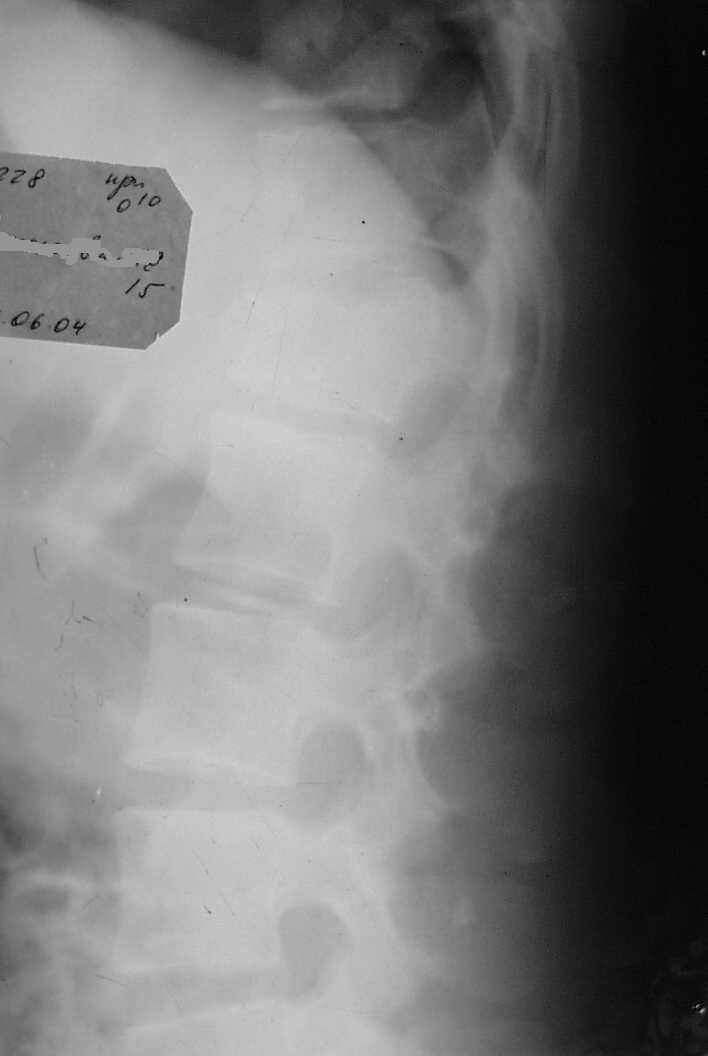

В травматологическое отделение поступила девочка 15 лет, после осмотра нейрохирургом с диагнозом Компрессионный перелом L1 Травма от 12/06-04 падение со скалы. Отделение не занимается оперативным лечением травм позвоночника. Нейрохирурги отправляя больную в дежурный стационар рекомендовали консервативное лечение.На момент осмотра и на настоящий момент неврологических растройств нет,девочка активно занимается ЛФК по методике, находится на щите с реклинирующим валиком.Прошу помочь разобраться нужна ли операция,где её можно сделать,сколько это будет стоить и в какой период,если необходима операция её надо делать.R-снимки прилагаются.Заранее благодарен. С уважением.Землянский А.А.

Обратите внимание на грыжи Шморля.

Нет ли у нее болезни Шейерманна-Мау?

Компрессия конечно приличная, но такие переломы довольно успешно лечатся консервативно по методике Гориневской-Древинг с реклинирующим валиком под

Для решения вопроса о тактике лечения необходимо наличие компьютерной томографии (КТ).Если по ее данным определяется наличие вертебро-медуллярного конфликта, даже 1 степени, то при такой величине локальной кифотической деформации стоит провести оперативное лечение - транспедикулярную фиксацию конструкцией "Синтез", что позволит максимально полно устранить имеющуюся деформацию, произвести закрытую декомпрессию, надежную стабилизацию. Кроме того, это позволит не позднее чем через 2 недели активизировать больную, т.е. разрешить ходьбу в корсете. Если вертебро-медуллярного конфликта нет, то тогда возможно консервативное лечение на реклинаторе не менее 1 мес, затем консервативное лечение - массаж, магнит, электростимуляция мышц спины и т.д.

Показанием к оперативной стабилизации поврежденного сегмента позвоночника является нестабильный характер перелома в сочетании с неврологическими расстройствами или без таковых. Косвенно по обычной Рг грамме можно оценить стабильность по величине компрессии тела позвонка: если более 50%, то наиболее вероятно вовлечение задней колонны сегмента, соответственно, перелом расценивается как нестабильный и нуждается в транспедикулярной фиксации. Хотя выбор только задней стабилизации при компрессии, превышающей 50% высоты тела позвонка кажется спорным и спинальные хирурги сочетают заднюю фиксацию с передним корпородезом.

В данном случае похоже, что степень компрессии менее 50%,поэтому при отсутствии неврологических расстройств нейрохирурги от оперативной фиксации позвоночника отказались. Что бы ясно представлять себе характер повреждения неплохо бы было сделать КТ Т12-Л1 и если дужки и суставные отростки не повреждены, то вполне можно обойтись и без хирургии.